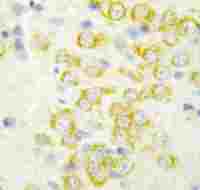

IHC-P analysis of human lung adenocarcinoma tissue using GTX79146 ALK (phospho Tyr1586) antibody.